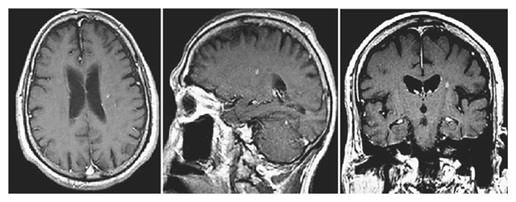

A 74-year-old right-handed, diabetic man with hypertension, renal dysfunction, and coronary artery disease requiring antiplatelet medication was diagnosed with non-small cell lung cancer with brain metastases. He was treated with radiation and chemotherapy for his lung cancer and SRS for the brain metastases in the left parietal and right frontal region, with each lesion receiving 20 Gy. One year later, a new intracranial lesion in the left centrum semiovale (adjacent to the previously treated left parietal lesion) measuring 4 mm in maximum diameter was treated with 20 Gy SRS (fig. 1). The SRS procedure was LINAC based using a multileaf collimator (mLC) with no other details of the procedure being available. Ten months following SRS, he presented with drooling, dysphasia, and slurred speech. Evaluation with magnetic resonance imaging (MRI) revealed that the centrum lesion had increased to 20 mm in maximum diameter. Additionally, there was significant perilesional edema and associated mass effect (fig. 2). A positron emission tomography-computed tomography (PET-CT) scan showed that the lesion was hypometabolic, and diffusion-weighted imaging (DWI) revealed restricted diffusion within the lesion, which was suggestive of radionecrosis.

74-year-old gentleman with non-small cell lung cancer and newly diagnosed brain metastasis in the left centrum semiovale treated with SRS (20 Gy). Pre-SRS axial, sagittal, and coronal contrast-enhanced T1 images showing a small contrast-enhancing lesion without perilesional edema identified during follow-up for treatment of the primary cancer.

74-year-old gentleman with non-small cell lung cancer and newly diagnosed brain metastasis in the left centrum semiovale treated with SRS (20 Gy). Pre-SRS axial, sagittal, and coronal contrast-enhanced T1 images showing a small contrast-enhancing lesion without perilesional edema identified during follow-up for treatment of the primary cancer.